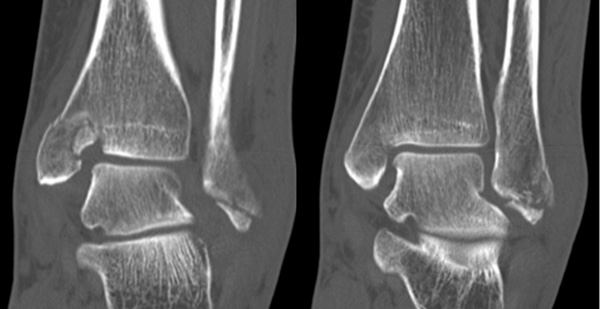

Liegt eine Fraktur des oberen Sprunggelenks vor, ist sowohl zur Entscheidung für ein konservatives oder operatives Vorgehen, als auch zur Operationsplanung, ein ausreichendes Verständnis der Fraktur und ihrer Morphologie notwendig. Insbesondere bei komplexen Verletzungen ist dafür die konventionelle Röntgenaufnahme in vielen Fällen nicht ausreichend. So konnten z.B. Black et al. zeigen, dass die operative Strategie zur Versorgung von OSG-Frakturen in 24% basierend auf einer zusätzlichen CT-Bildgebung relevant geändert wurden 7. Dies betraf die Lagerung, die Wahl des Zuganges und die Art der osteosynthetischen Versorgung. Besonders häufig änderte sich das Vorgehen bei Verletzungen des medialen (21%) und des posterioren Malleolus (15%). Darüber hinaus führten dislozierte (dislozierte Frakturen 31% vs. nicht-dislozierte Frakturen 20%) oder komplexe Frakturen (Trimalleolar-Frakturen 29% vs. Unimalleolar-Frakturen 10%) besonders häufig zu relevanten Änderungen des operativen Vorgehens. Die Computertomographie ist daher, insbesondere bei Bi- und Trimalleolar-Frakturen, essentiell für das Verständnis der Fraktur und somit für die Planung und Durchführung der Operation. In Abbildung 4 und 5 sind exemplarisch ein Röntgen- und ein CT Befund gegenübergestellt.